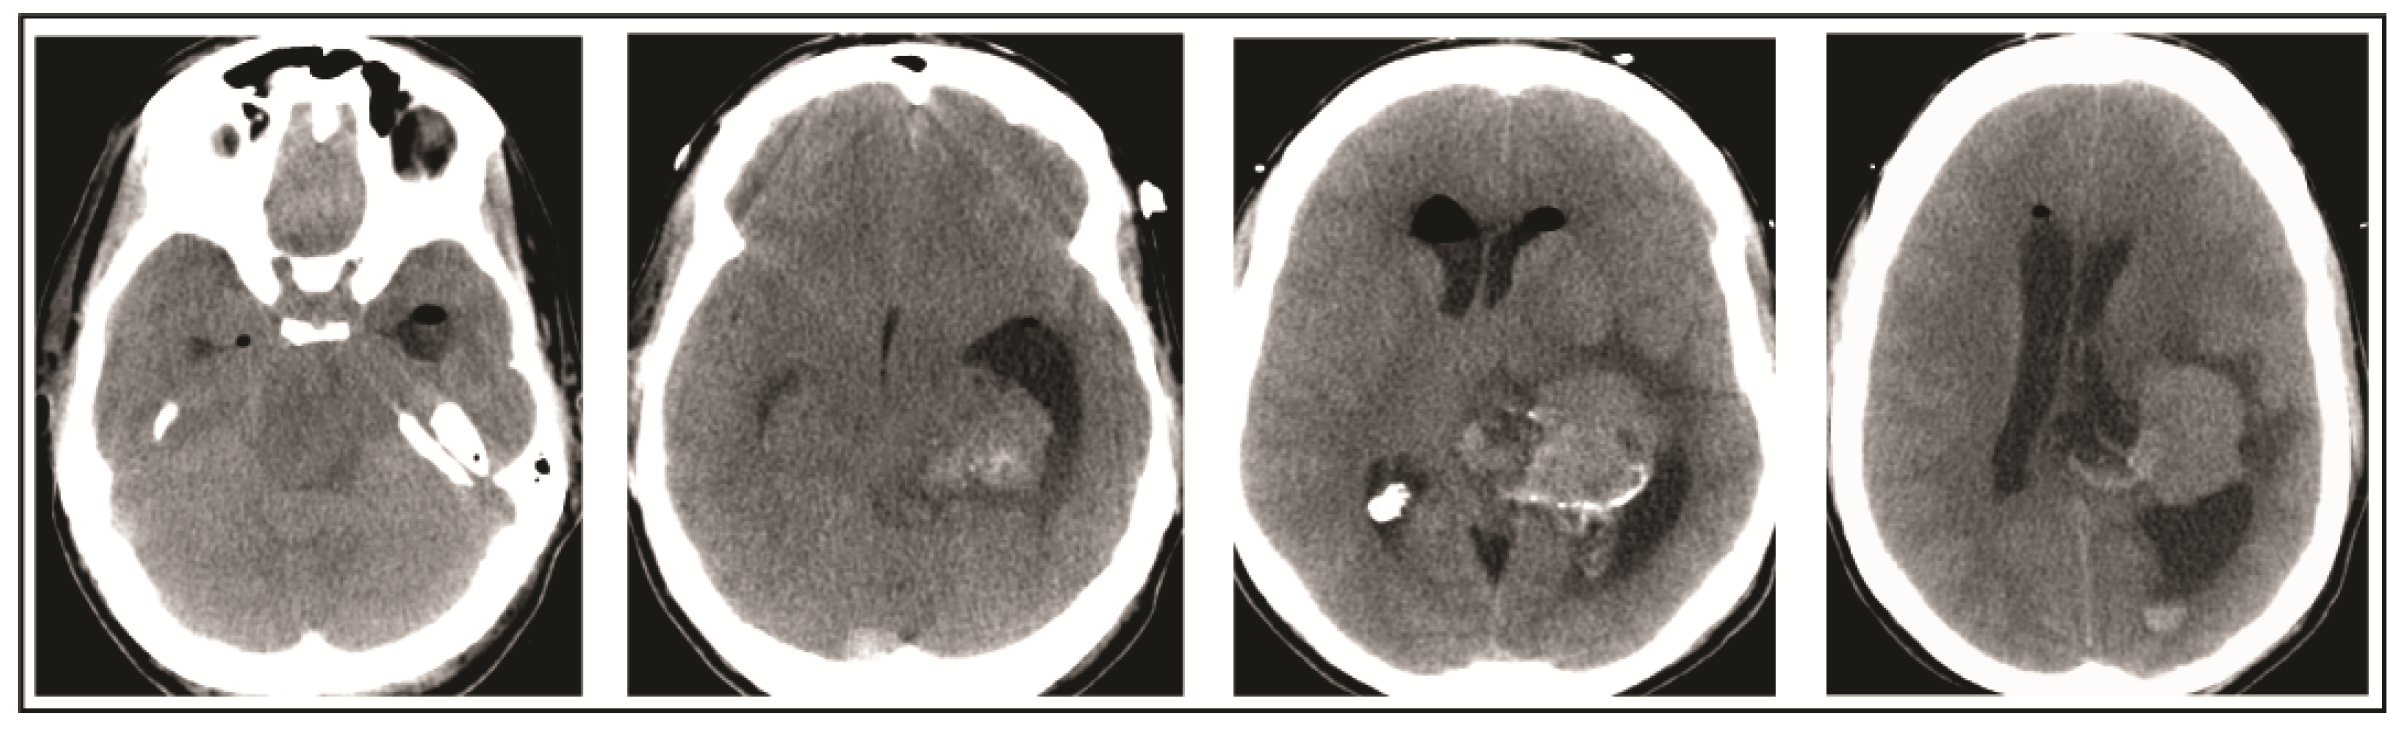

2. Case Presentation